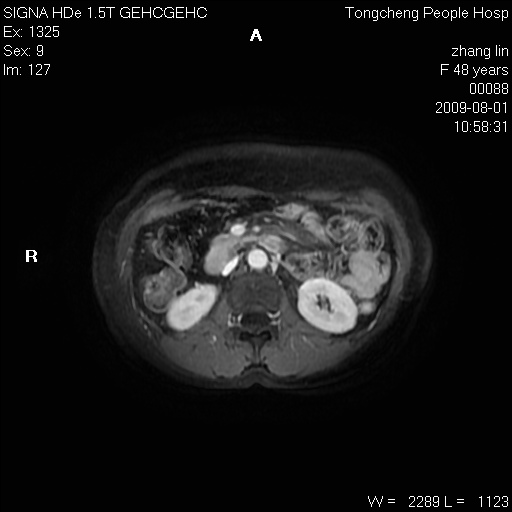

女,48岁。健康体检,彩超发现右肾占位性病变。平素健康。

临床诊断:右肾占位性病变,性质待定(囊肿?肿瘤?)。

上中腹部mr平扫+增强扫描,图像如下:

右肾上极见一类圆形病灶,t1wi呈等信号t2wi呈等高混杂信号,三期增强无强化,边界清---考虑囊肿出血。

同反相位均表现为等信号,病变无强化,考虑含蛋白的囊肿可能,弥散加权相或许有些帮助,

肝囊肿

慢性胆囊炎